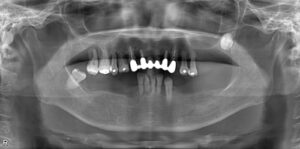

上顎オールオン6/下顎ロケーター義歯 症例

BEFORE AFTER 72歳女性/上顎6本・下顎2本 【治療内容】 上下顎ともに骨吸収が進み、入れ歯が合わなくな…